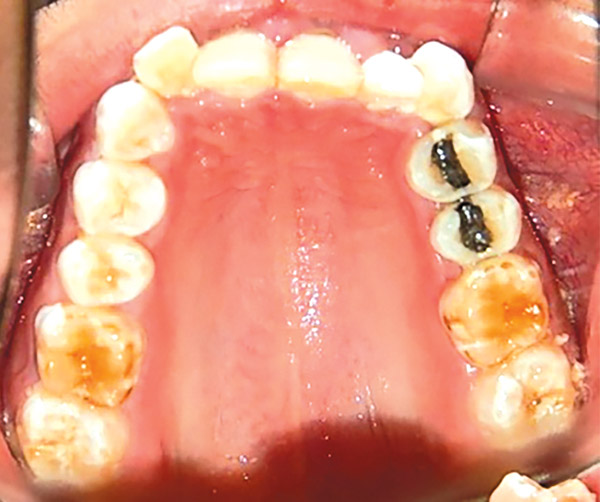

En las fotografías intraorales se muestra la fluorosis dental Tf4 y Tf7, las relaciones molares clase II molar y canina bilateral (Figura 3 y 4), el apiñamiento severo superior e inferior, con el órgano dental 35 en infraoclusión. El overbite aumentado y las líneas medias dentales no son coincidentes (Figura 5), las formas de arco superior e inferior son cuadradas (Figura 6 y 7).

Figura 6. Oclusal superior.

Figura 7. Inferior.